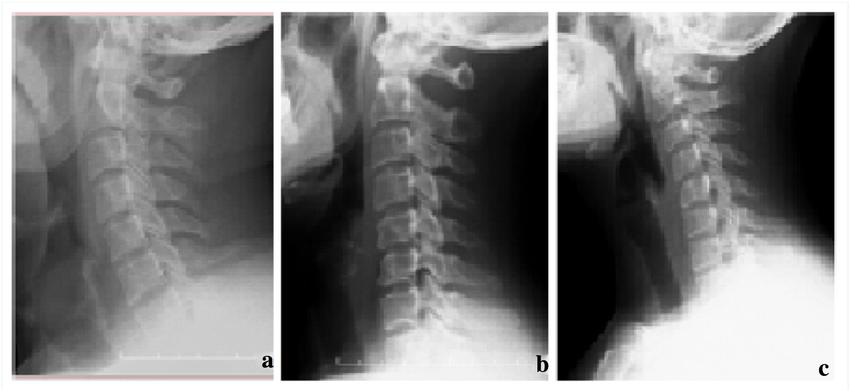

颈椎 X 光平片(正侧位)上面检查可以看到颈椎生理曲度的减少、消失、甚至是反弓,骨质增生、颈椎生理曲度异常、椎间狭窄及变形等,看不了肌肉、韧带等软组织,但胜在便宜快捷且提供的信息较多。如果有头肩颈疼痛并有压痛点、有颈部或上肢麻木疼痛、眩晕眼花耳鸣手麻等症状,别犹豫了,去医院吧。

来源:

上图中 a 为正常颈前凸;b 为颈前凸丧失;c 为颈驼背。